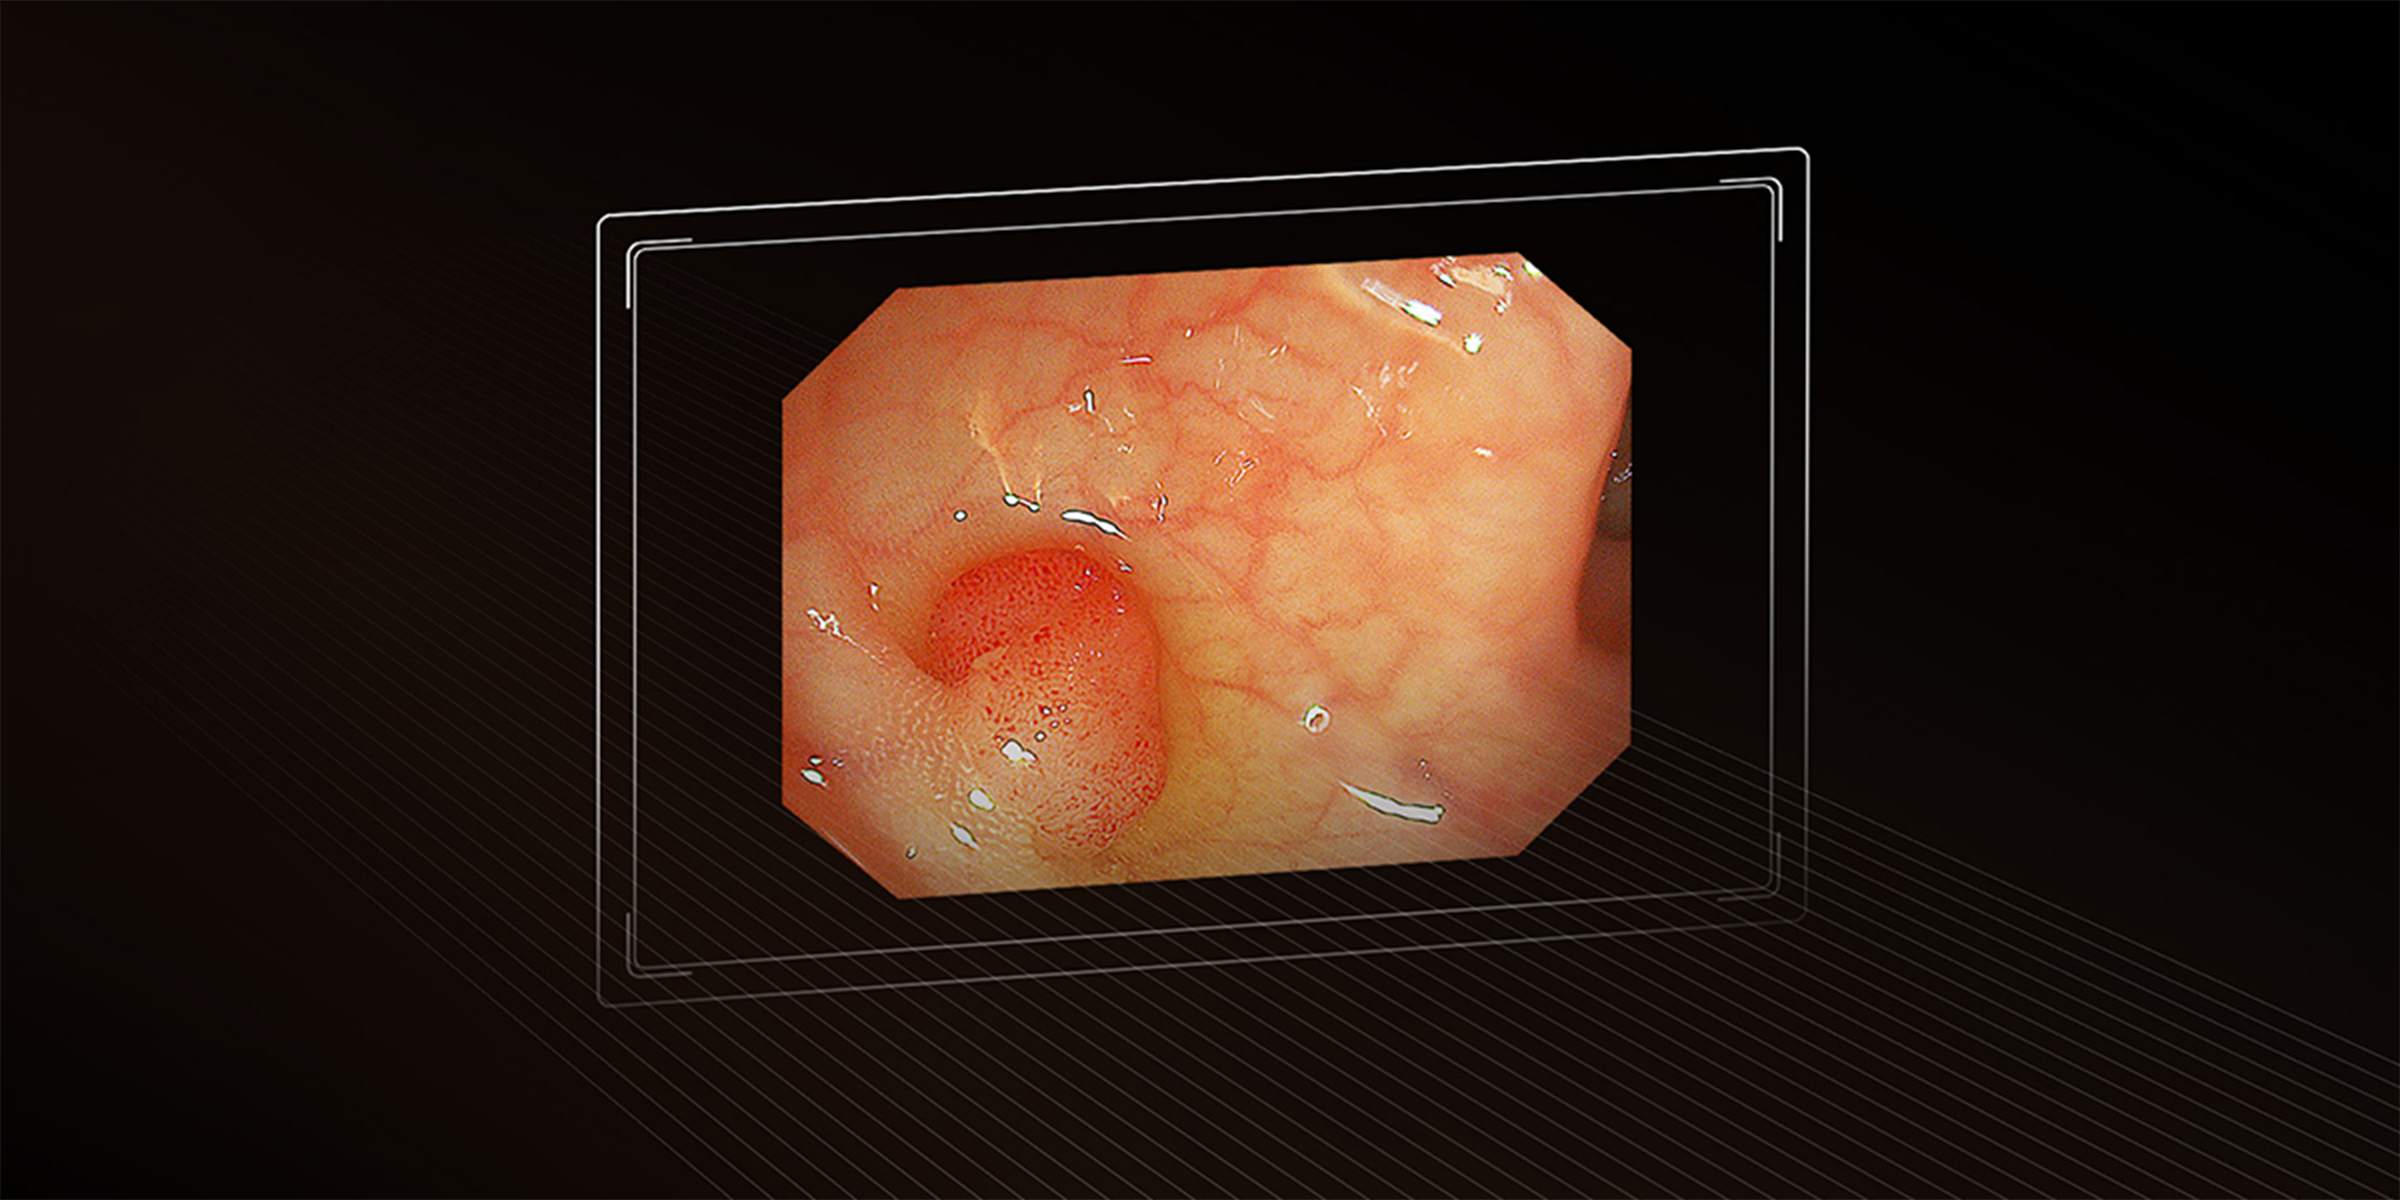

Видеогастроскоп Aohua VGT−Q30J

Высококачественное и высокотехнологичное передовое медицинское оборудование, предназначенное для проведения эндоскопических исследований верхних отделов желудочно-кишечного тракта, для диагностики и лечения заболеваний пищеварительного тракта. Модель оснащена видеокамерой с разрешением Full HD, что обеспечивает максимально точное, чёткое и детализированное изображение. Гибкая и тонкая вставка позволяет проводить процедуры с минимальным дискомфортом для пациента. Поддерживает расширенные функции записи и передачи данных, делая его незаменимым инструментом для современных эндоскопических кабинетов.

- Разрешение Full HD, что гарантирует точную визуализацию исследуемых областей.

- Высокая точность диагностики – благодаря Full HD видеокамере, медицинские специалисты могут получить детализированное изображение слизистой оболочки пищевода, желудка и двенадцатиперстной кишки, что существенно улучшает качество диагностики и лечения.